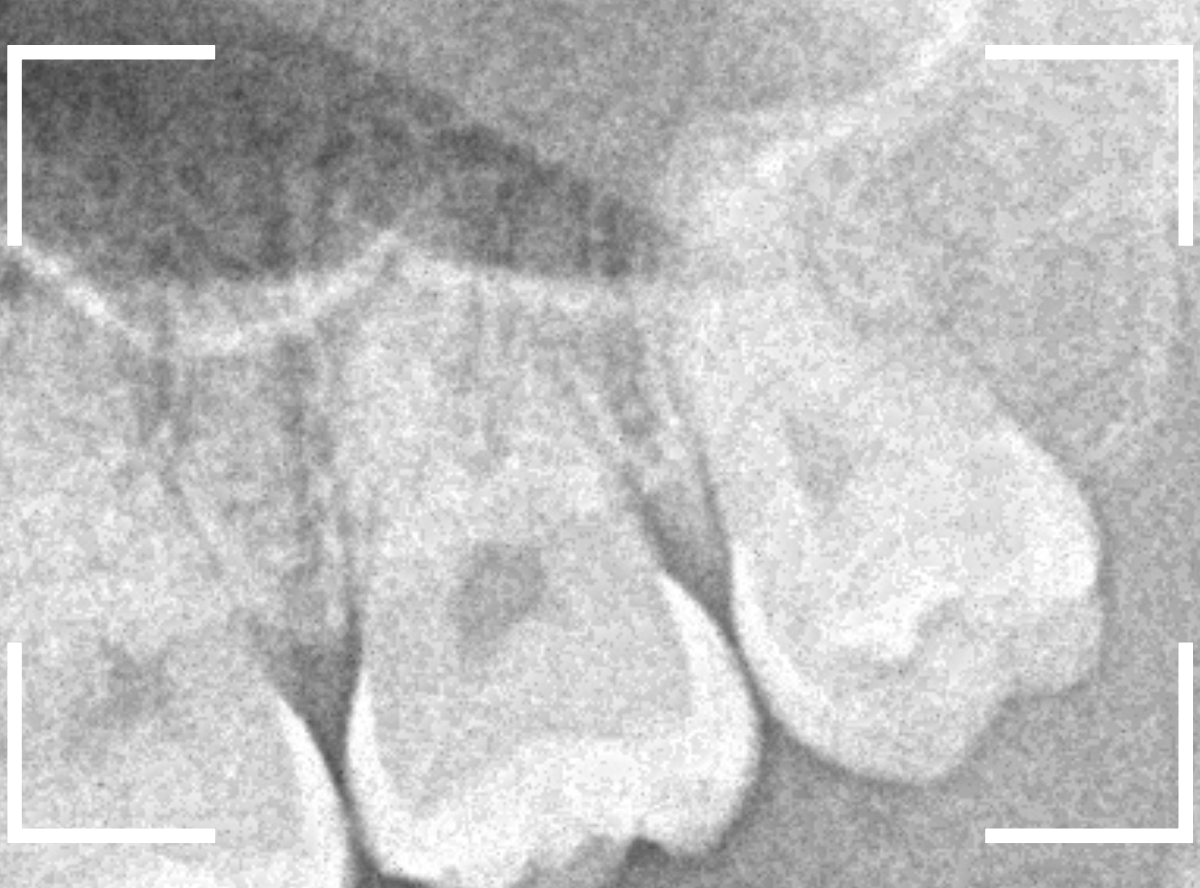

抜歯後に長期間お痛みが出たり、経過観察が必要な難しいおやしらずの抜歯ならまだしも、簡単なおやしらずの抜歯を避けてしまったがために、他の歯に悪影響を与えてしまったもったいない例も多々見てきました。

ここでは、比較的簡単なおやしらずの抜歯の例を中心にご紹介します。

このようなおやしらず、あなたはありませんか?